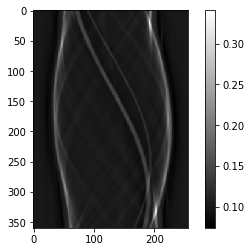

# Question 3

# SPR

SPR = scatter / primary

plt.figure()

plt.imshow(SPR.T)

plt.colorbar()

1

<matplotlib.colorbar.Colorbar at 0x7fce4e72f880>